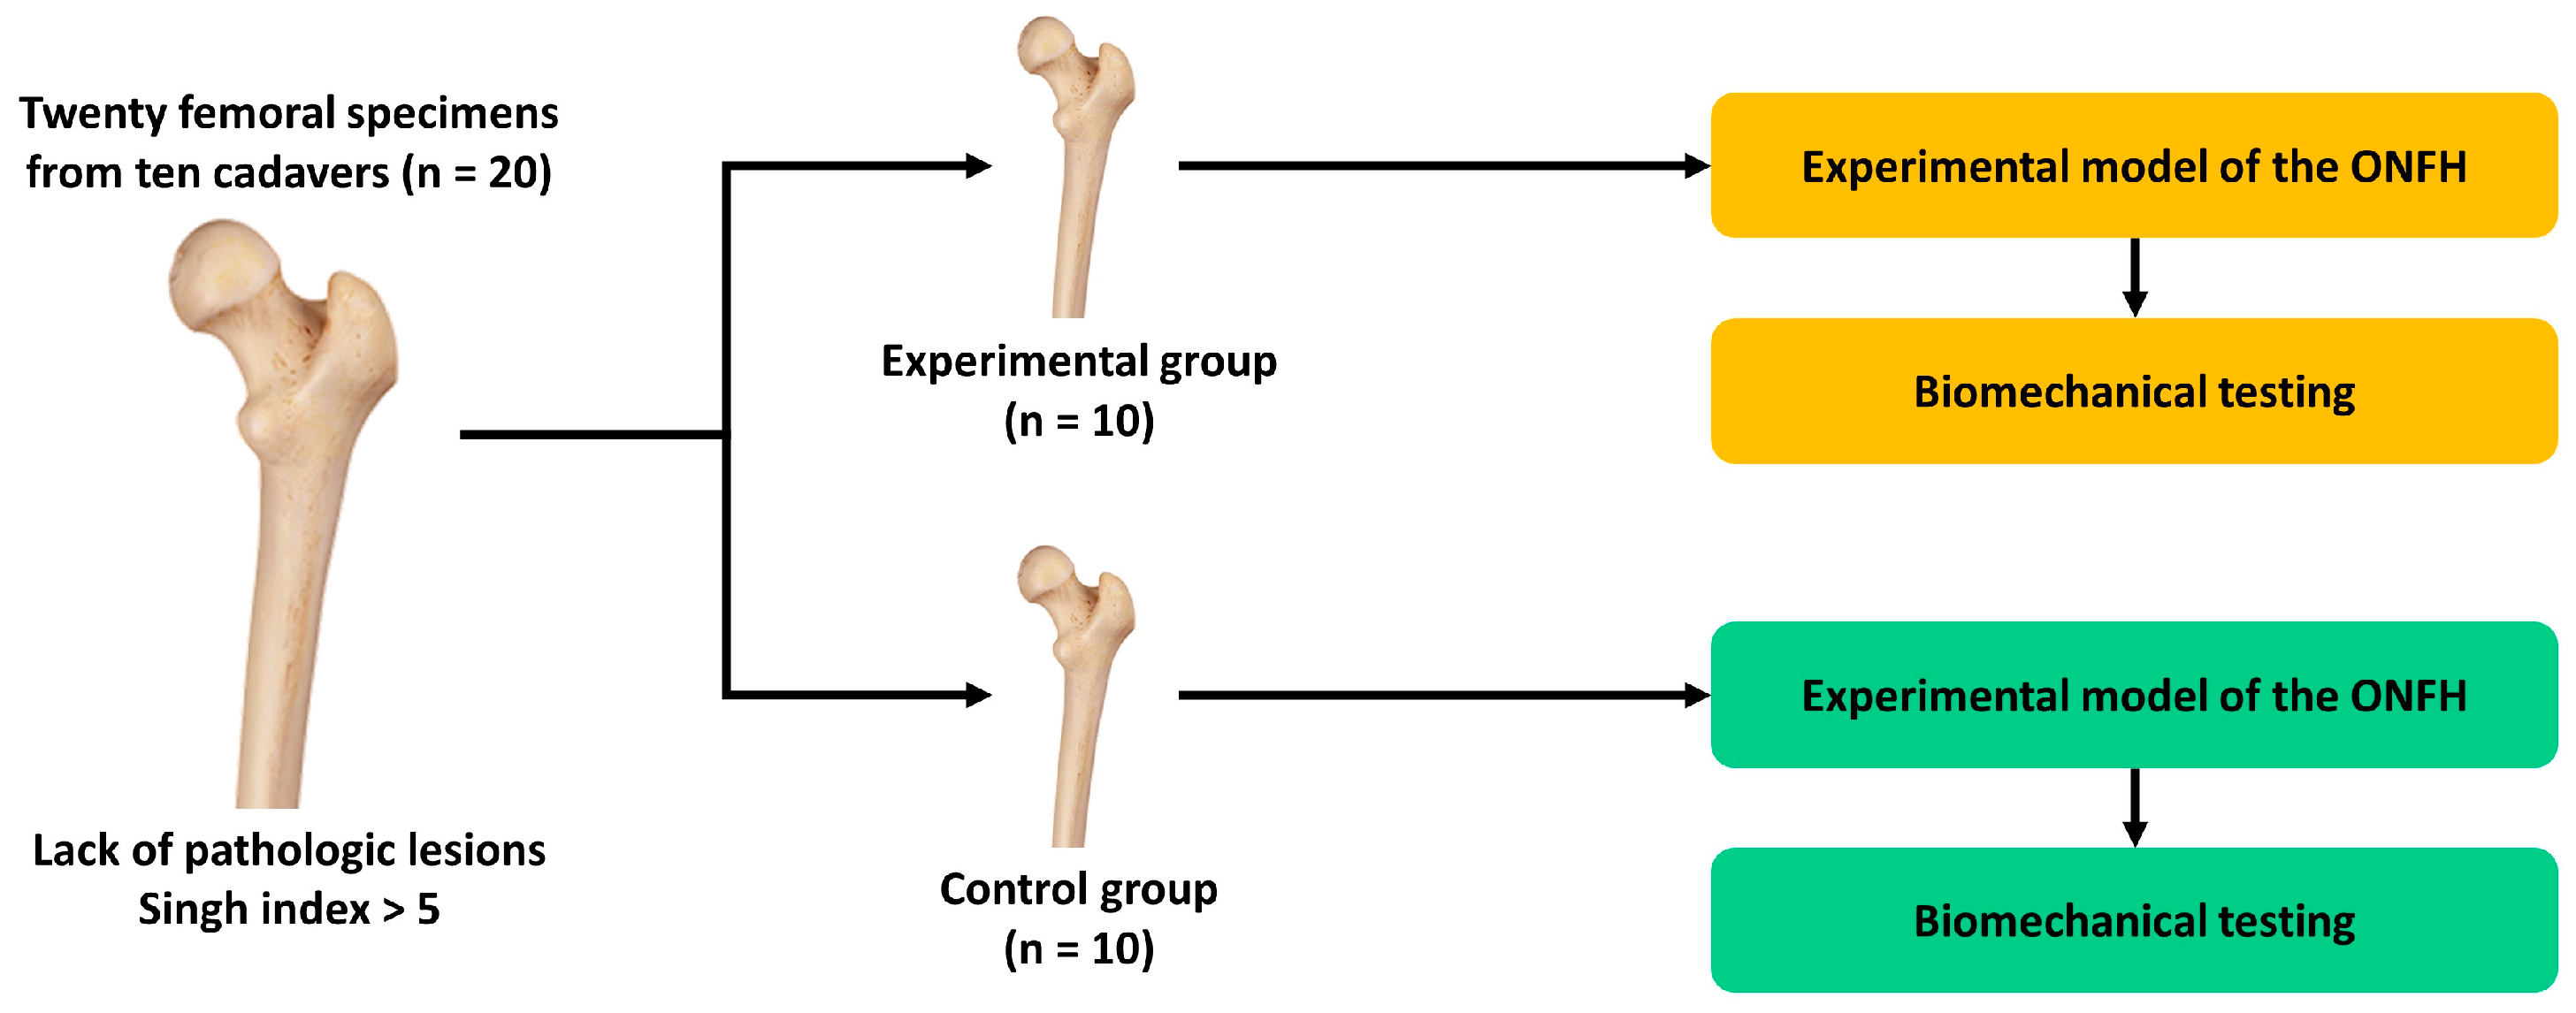

2. Materials and Methods

2.1. Experimental Materials and Setting